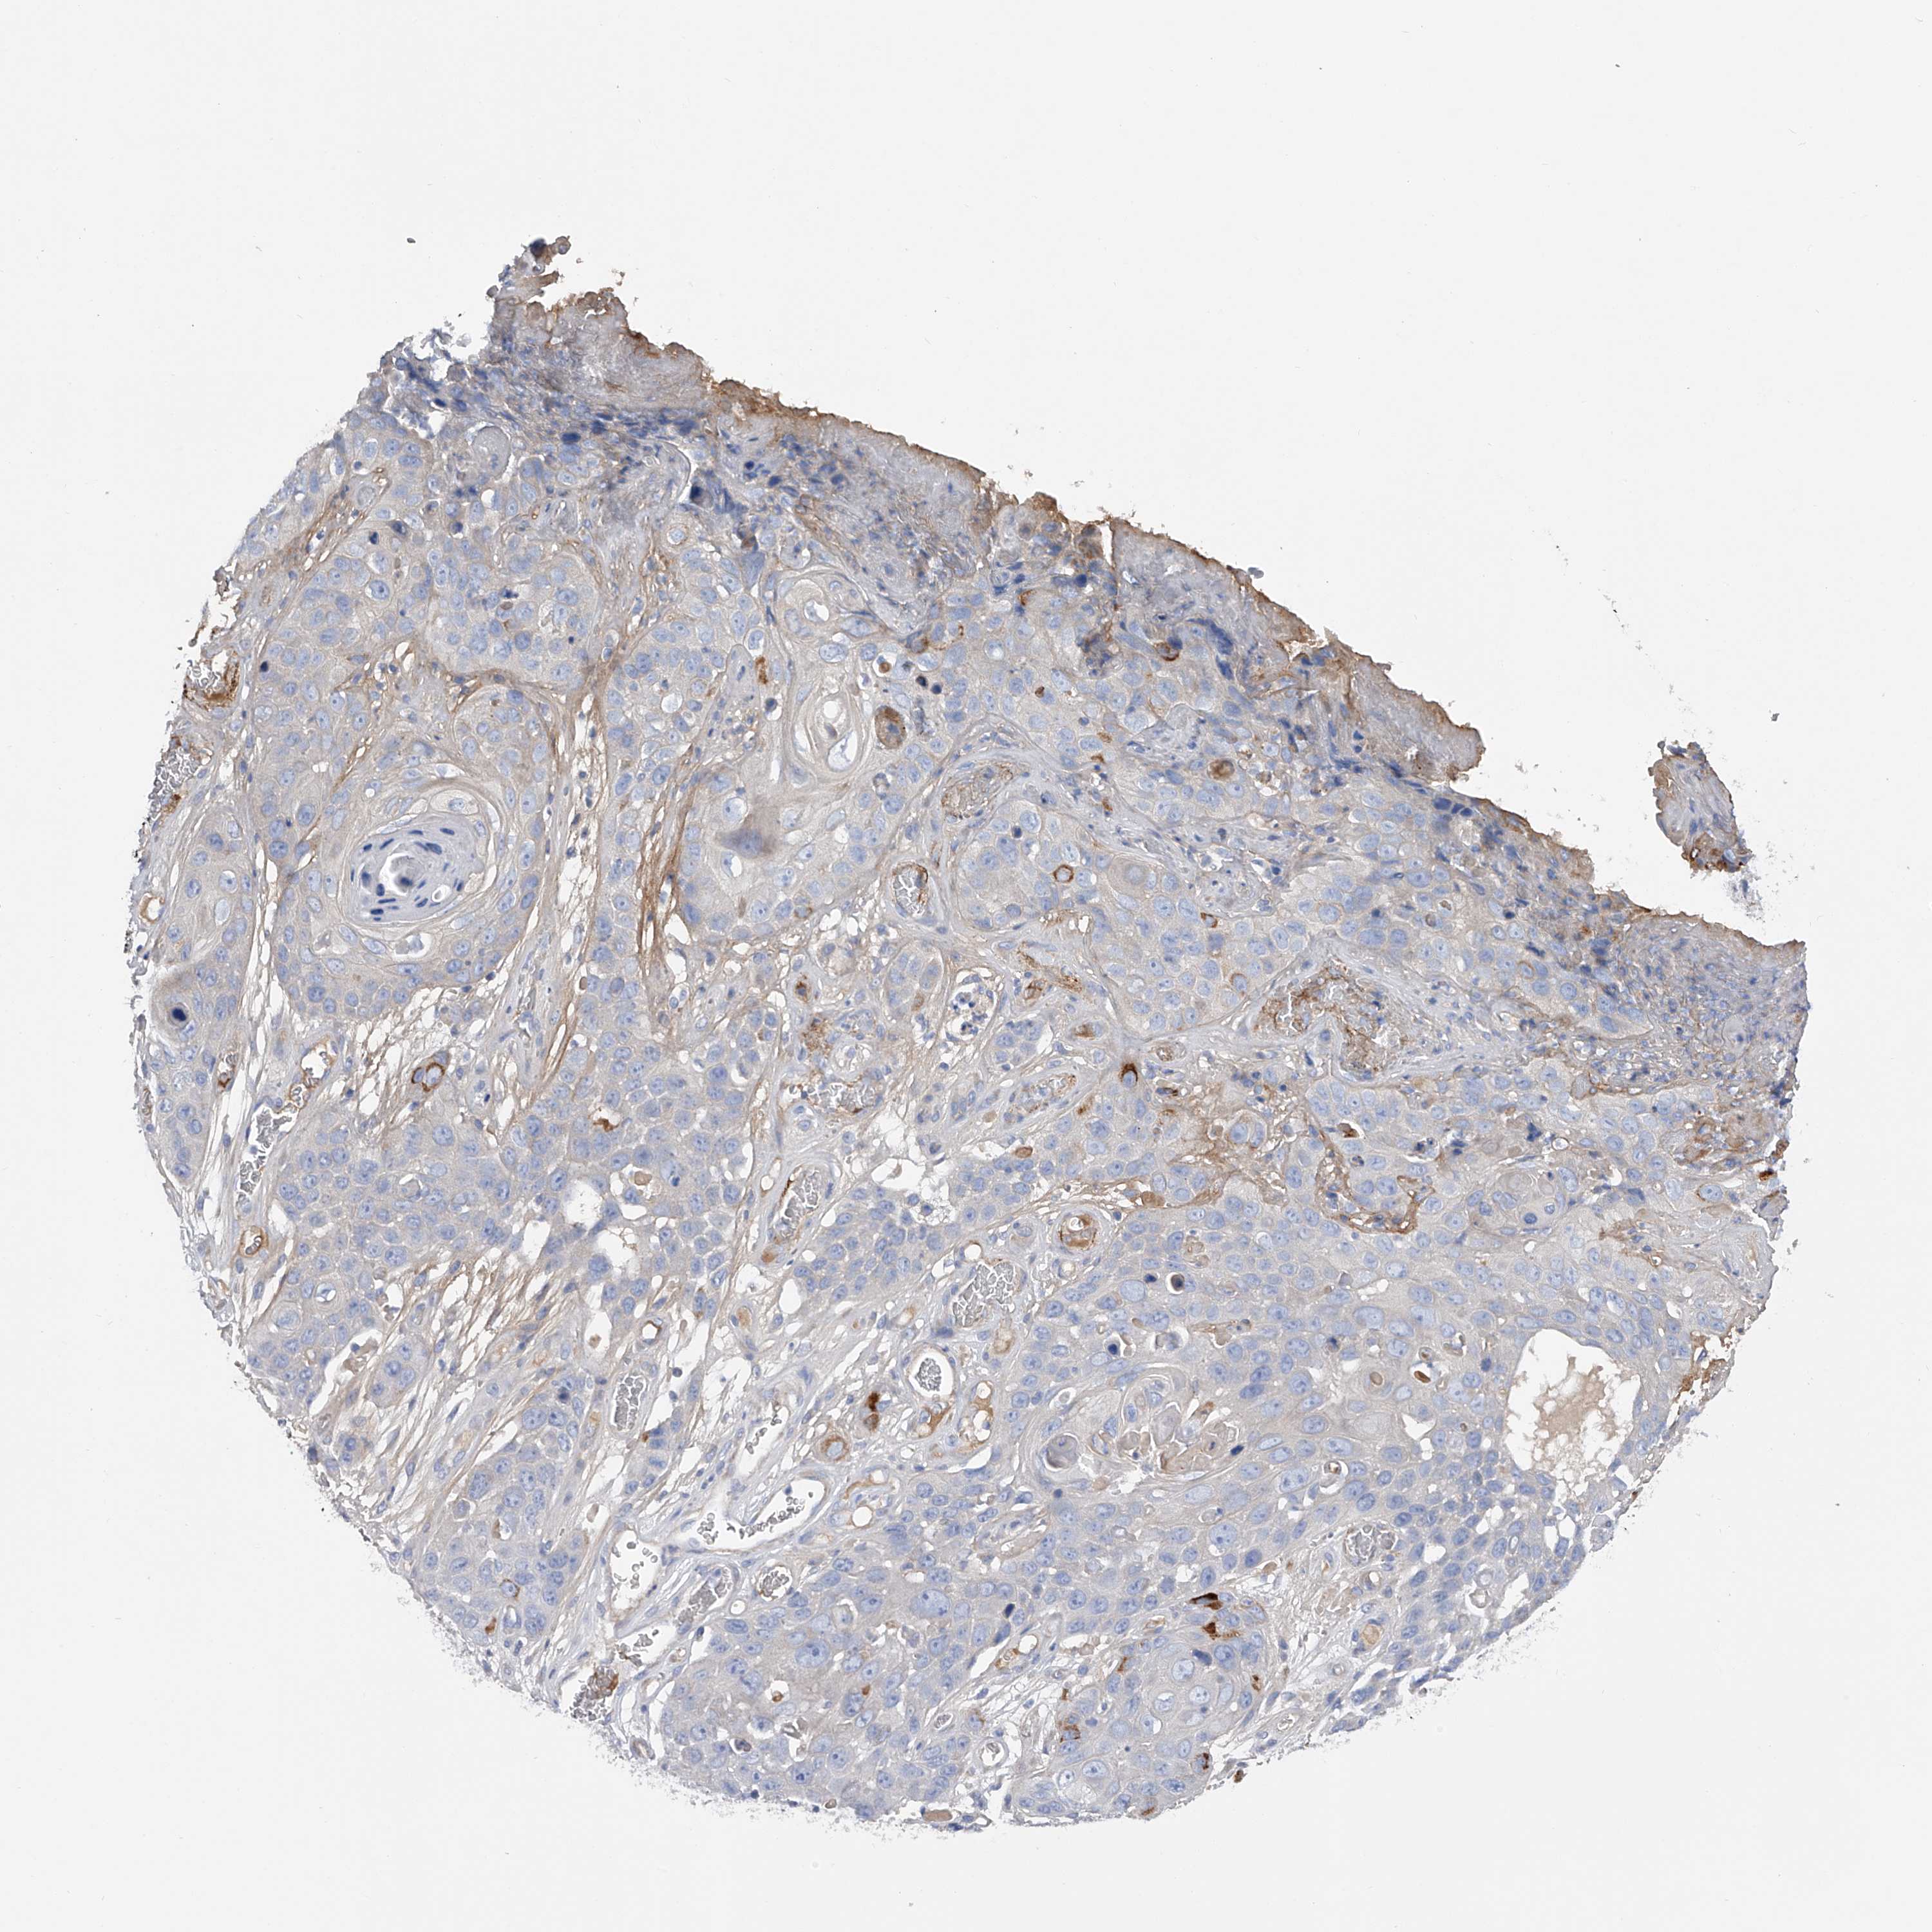

CANCER SKIN CANCER Show tissue menu

Basal cell and squamous cell cancer

SKIN CANCER - Protein expressioni

A mouse-over function shows sample information and annotation data. Click on an image to view it in a full screen mode. Samples can be filtered based on level of antibody staining by selecting one or several of the following categories: high, medium, low and not detected. The assay and annotation is described here.

Each image is clickable and will lead to virtual microscopy that enables deeper exploration of all samples and also displays staining intensity scores, fraction scores and subcellular localization as well as patient and tissue information for each sample.

Antibody HPA030105

Antibody HPA030106

Antibody HPA030107

Basal cell carcinoma

Squamous cell carcinoma, NOS

Squamous cell carcinoma, metastatic, NOS